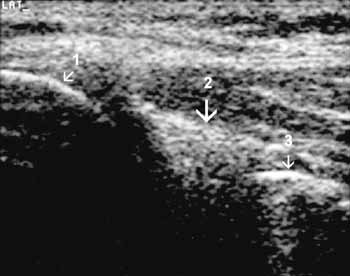

Рис. 12. Коленный сустав в норме. Задняя поверхность сагиттальная проекция.

1 — латеральный мыщелок бедренной кости, 2 — задний рог латерального мениска,

3 — большеберцовая кость.